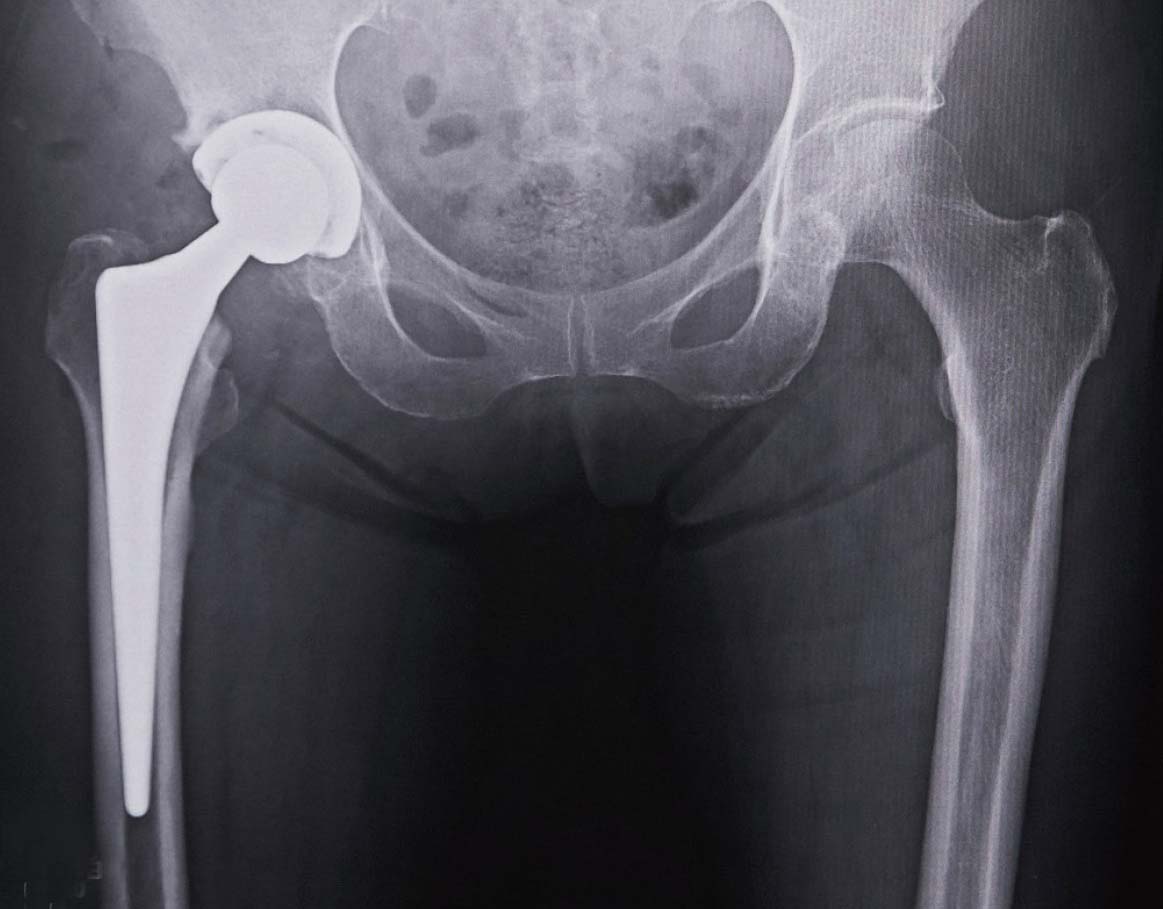

人工股関節の一例

人工股関節置換術後のレントゲン

手術は、全身麻酔をかけた上で股関節の前外方を切開し、変形した大腿骨頭を切除します。さらに、寛骨臼を削って代わりとなる金属を骨盤側に設置。大腿骨側にはステムと呼ばれる金属を差し込んで固定します。その後、ポリエチレンの人工軟骨、セラミックの骨頭を入れて、関節の動きや安定性を確認した後で、傷を縫合します。

その通りです。使用する人工股関節の素材はポリエチレンとセラミックですが、極めて摩耗に強く、最近のデータによると25年後も90%以上が問題なく使用されています。20年前なら、人工関節の耐用年数は10~15年程度といわれ、再置換術が大変なことから、手術の適用年齢は65歳以上とされていました。現在、40~50代でも手術を受ける人が増えてきているのは、人工関節自体が長持ちするようになったことが大きく寄与しています。若い患者さんでも、一度人工股関節にすれば生涯そのまま過ごすといったことが十分可能です。